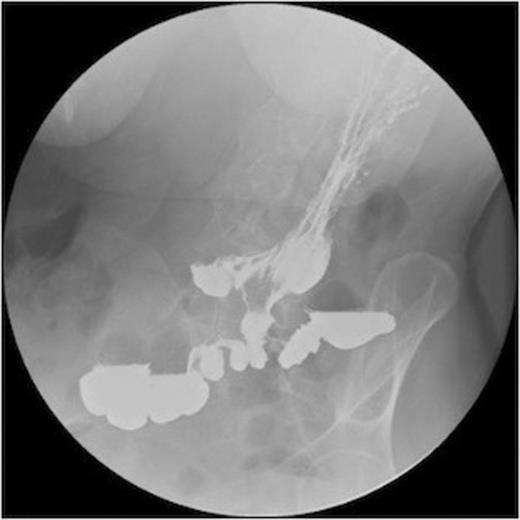

A series of radiographs from barium swallow demonstrating gastro-colic fistula